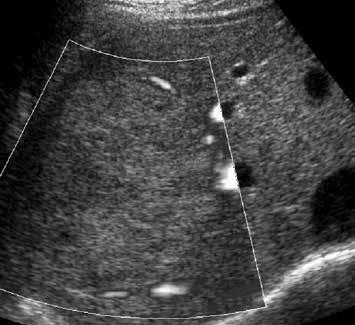

V UZ obraze je patrné ostře ohraničené, homogenně hypoechogenní ložisko v S7 (17).